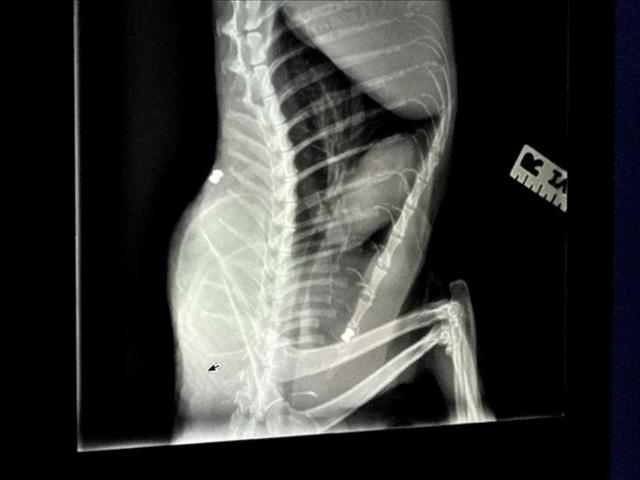

ภาพเอกซเรย์ของแมวอัลเบิร์ต แสดงภาพของกระสุนฝังอยู่ในหลังอย่างถาวร

โดยหนึ่งในนั้นเป็นแมวจร ซึ่งพีตาตั้งชื่อว่า “อัลเบิร์ต” ถูกยิงด้วยปืนบีบีกันในซอยใกล้ถนนเวสต์ 94 และเวอร์มอนต์ โดยกระสุนทำให้กระดูกแขนแตกและฝังอยู่ในกระดูกสันหลัง ปัจจุบันอาการอยู่ในขั้นทรงตัว แต่ไม่สามารถผ่าตัดนำกระสุนออกได้ เนื่องจากเสี่ยงต่อการเป็นอัมพาต และอาจต้องใช้ยาแก้ปวดพร้อมเดินกะเผลกไปตลอดชีวิต